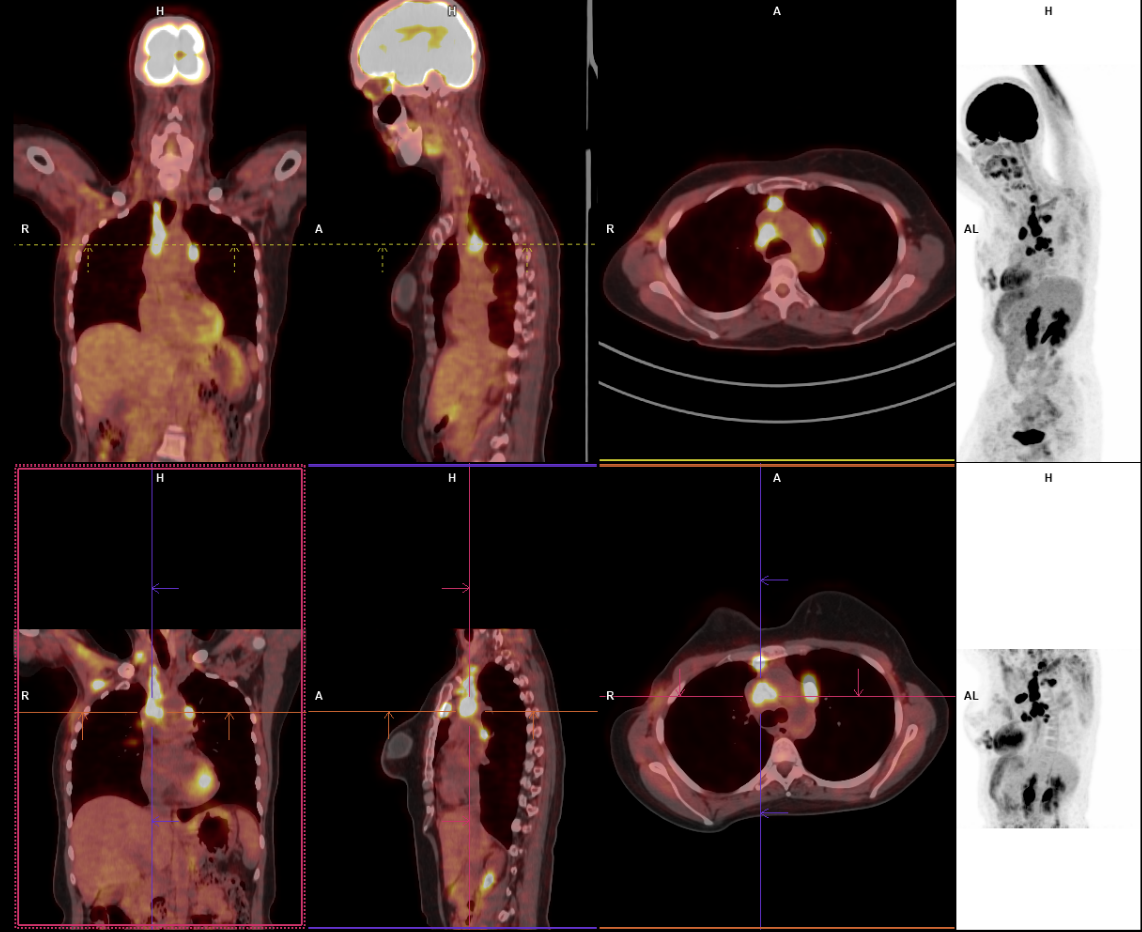

PET_CT_5oAno

PET-CT com FDG em paciente com câncer de mama. Observam-se focos de hipercaptação em linfonodos mediastinais, compatíveis com acometimento metastático. O exame demonstra a utilidade do PET-CT na detecção de doença sistêmica e no estadiamento oncológico.